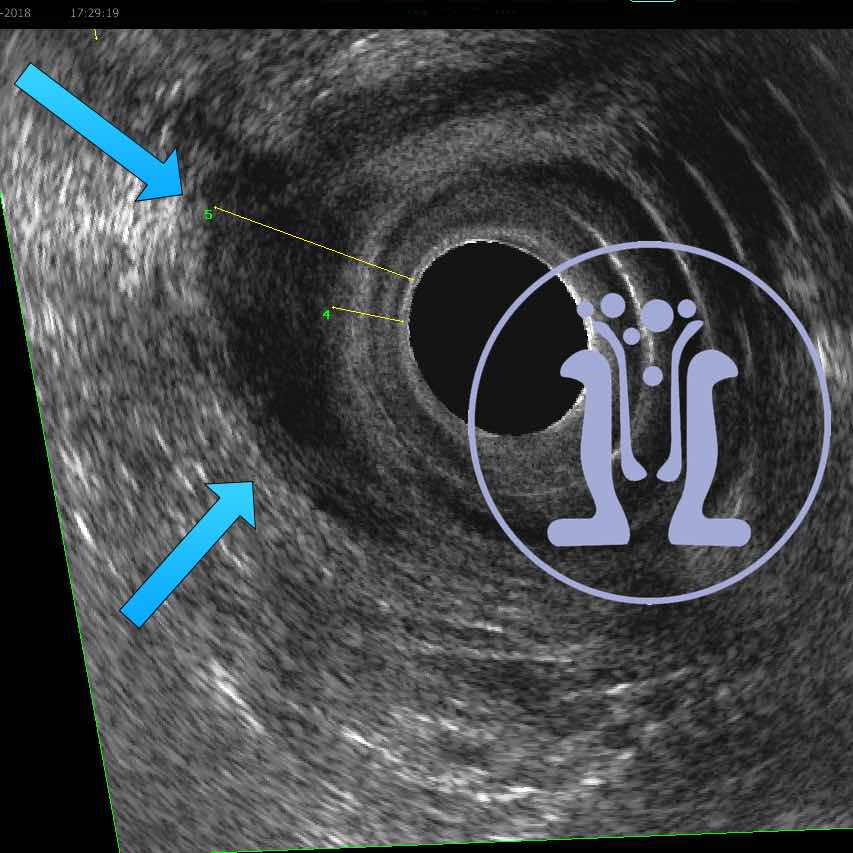

54 ετών κύριος αναφέρει εκροή πύου και φλεγμονής στη περίπρωκτικη περιοχη από 5 μήνες. Κλινικά ανευρέθηκε δερματικό στόμιο στην 3η ώρα. Στη δακτυλική εξέταση ανευρέθηκε ευμέγεθες στόμιο στην 6 ώρα. Με τη σκιαγράφηση του συριγγίου, το ενδοπρωκτικό υπερηχογράφημα επιβεβαιωσε την θέση του πρωκτικού στομίου και ταυτόχρονα έδειξε υψηλό συρίγγιο στην 6η ώρα με επέκταση έως 5 cm από το δακτύλιο του πρωκτού πίσω από την λήκυθο του ορθού.